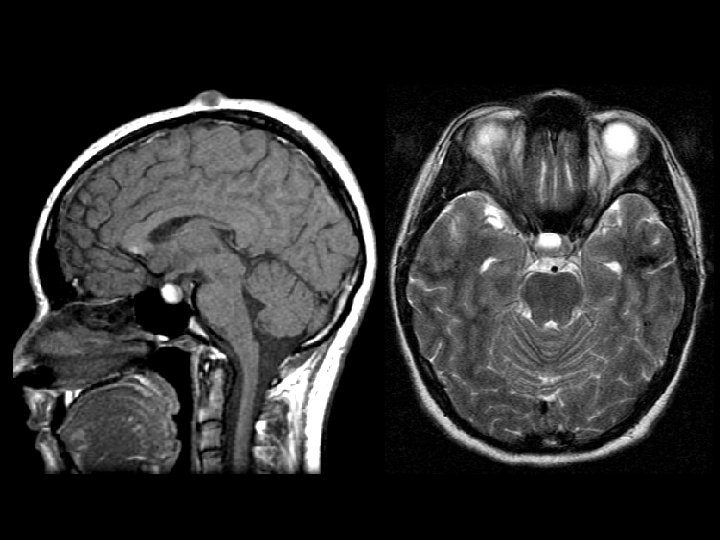

Rathke’s Cleft Cyst • Findings: – High T 1 & T 2 slightly expansile sellar lesion – Displaces normal pituitary tissue • Non-neoplastic remnants of Rathke’s pouch • majority are asymptomatic, symptoms include visual defects, pit insufficiency, headaches • Can be high or low T 1 but always high T 2 • Ddx: – Arachnoid cyst – Epidermoid – Pituitray adenoma – craniopharyngioma